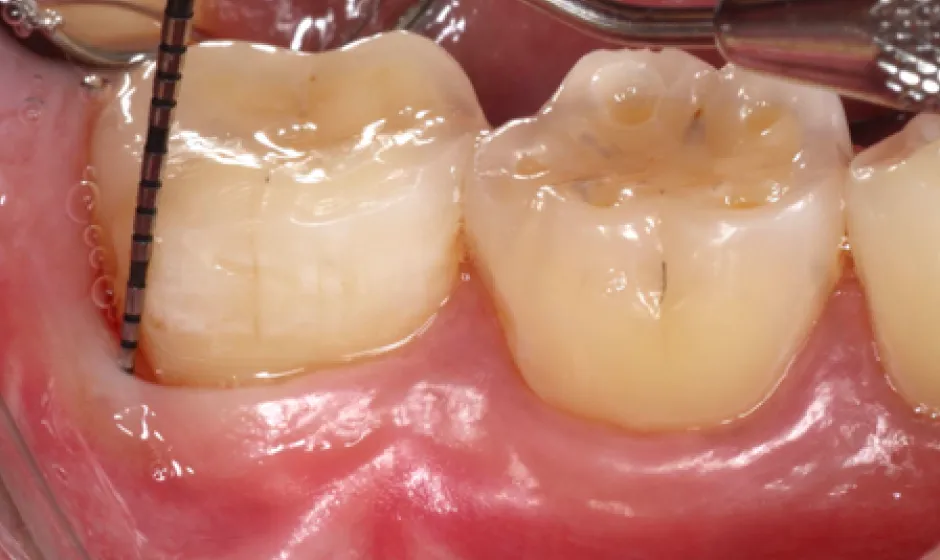

01精密根管治療

「抜くしかない」と言われた歯でも、根の中の感染を適切に抑えられる治療技術があれば、歯を残せる可能性があります。根管は非常に細く複雑で、わずかな取り残しが痛みや腫れの再発につながることもあるため、当院では必要に応じてCTやマイクロスコープを活用し、原因を見極めながら丁寧に処置を進めます。

大杉歯科医院が大切にしているのは、早く終える治療ではなく、歯を守る治療。津市で、できるだけ天然歯を残したい方の選択肢になれるよう取り組んでいます。症例1

- 治療名

- マイクロスコープとラバーダムを使用した精密根管治療

- 患者様

- 30代男性

- 執刀医

- Dr. 大杉

- 治療期間

- 3ヶ月

- 治療費

- 精密根管治療:130,000円(税込)

築造:40,000円(税込) - リスク

- 治療中〜治療後に痛みが出る場合あり

再感染・治癒不全の可能性

補綴後も定期管理が必要